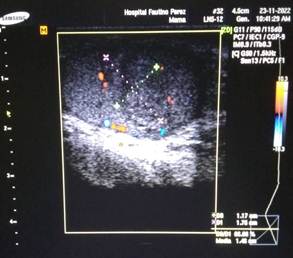

Scrotal Doppler ultrasound (Figure 1): showed a mixed, hypoechoic tumor mass located in the front part and upper pole of the left testicle, measuring 10 × 8 mm, with cystic areas inside and tiny calcifications. Color Doppler study showed increased internal blood flow (highly vascular), a pattern suggestive of germ cell tumor (Figure 2). On cross-sectional imaging, the solid nature of the lesion was seen, with irregular edges and no posterior acoustic shadow (Figure 3).

Figure 1: Scrotal Doppler ultrasound, longitudinal view. Shows a mixed hypoechoic mass at the upper pole of the left testicle (arrow), with internal cystic areas and tiny calcifications. Maximum diameter: 10 mm.